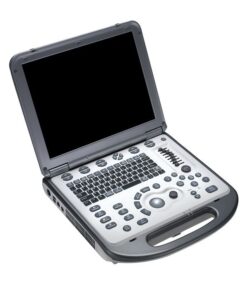

Hitachi Aloka F37 – Ultrasound System

Hitachi Aloka F37 Providing all that is needed in a versatile diagnostic ultrasound system, F37 is ready to be your partner.

Hitachi Aloka F37 thoroughly simple and compact. As a user-friendly diagnostic ultrasound system full of functional and ergonomic features, F37 is ready to be your partner.

Compact and Practical Design

Lightweight, small footprint, and ergonomic design: these features of the F37 enable nimble transport and comfortable examinations. The sophisticated 3E Platform is what makes the small size of the Hitachi Aloka F37 possible and because many functions are software based, the system is not only compact but also provides faster processing, lower power consumption, and future upgradeability.